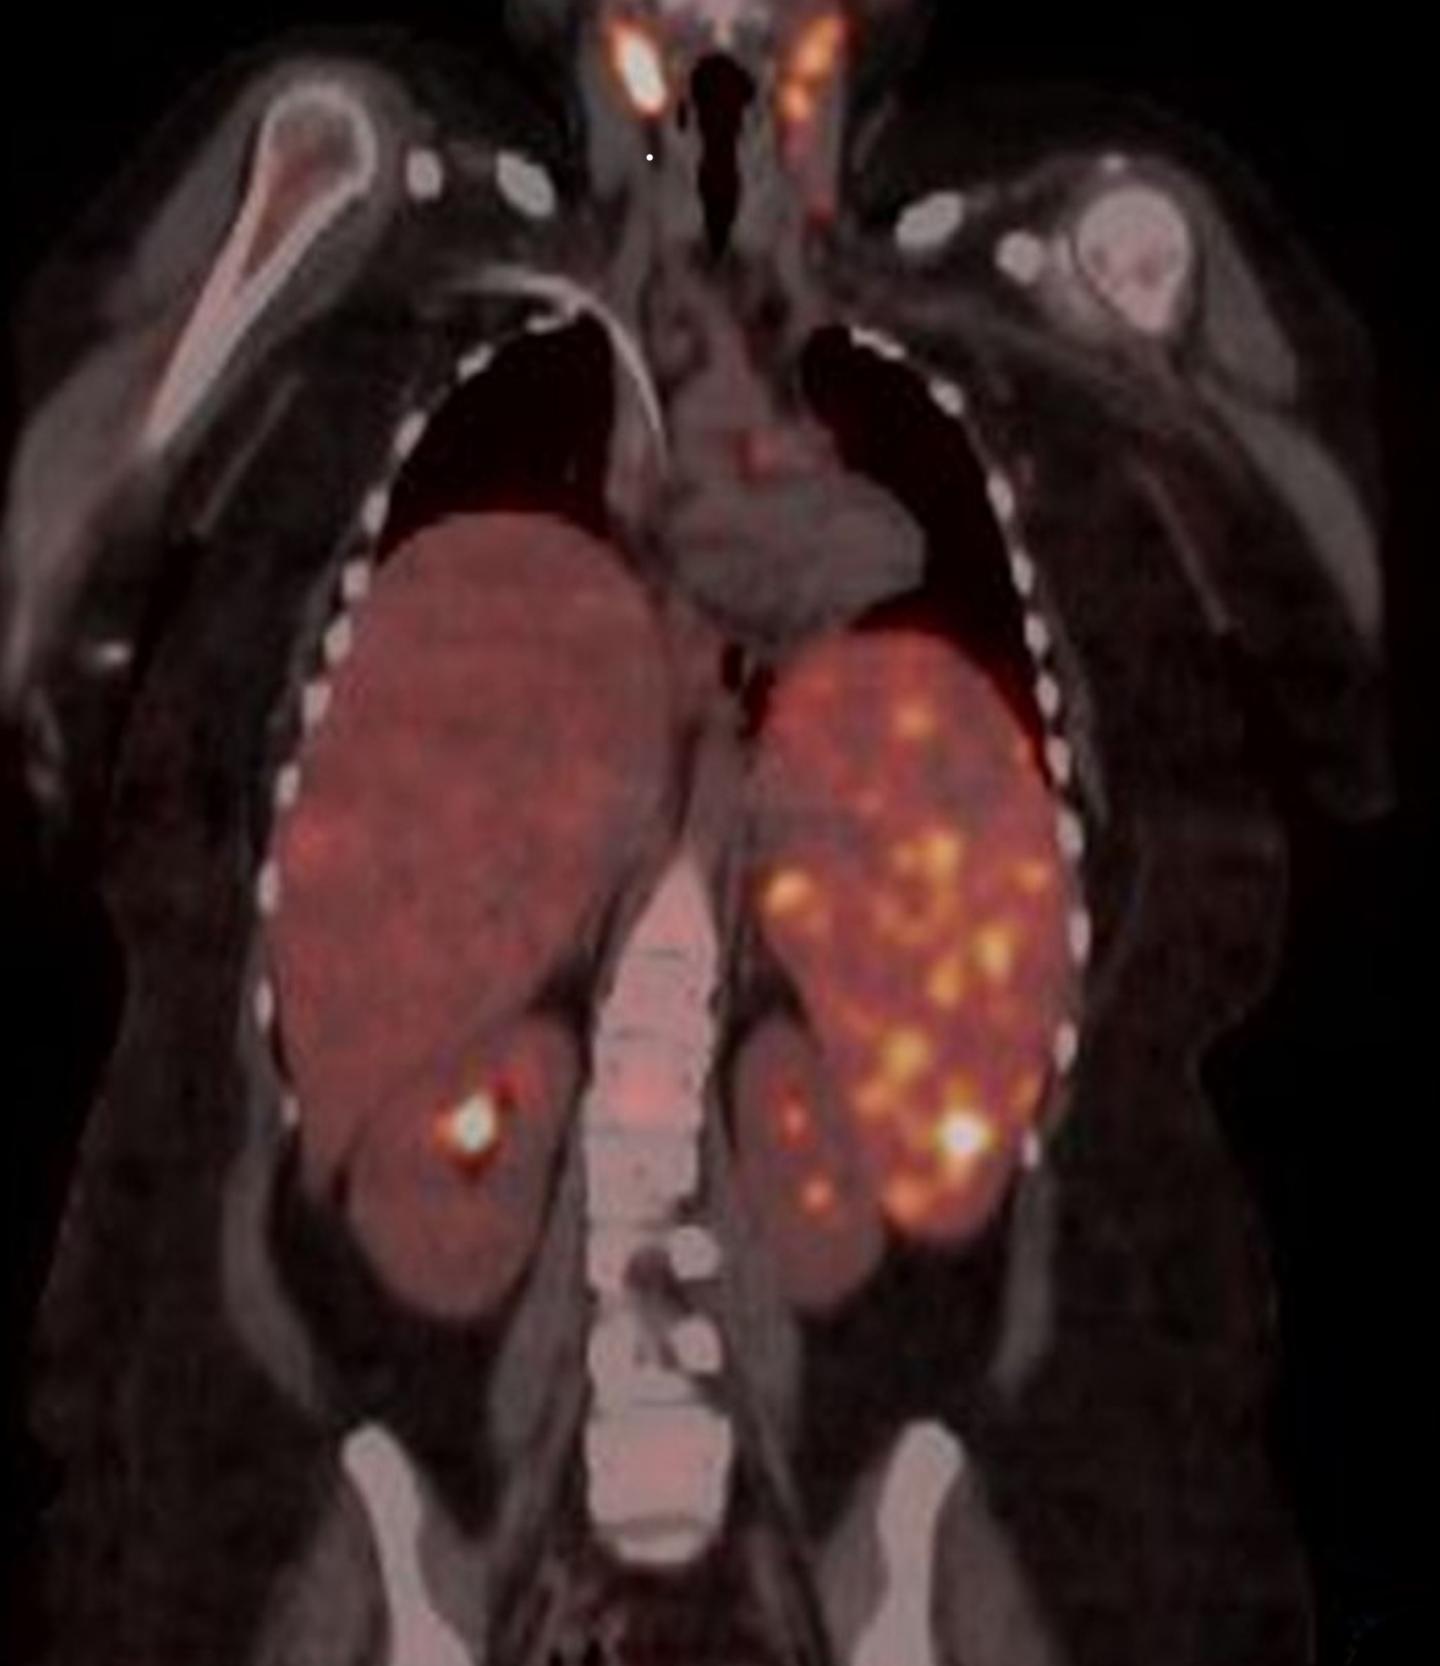

The diagnoses were based on the patients meeting current diagnostic criteria for the disease. Further investigations by physicians at Cincinnati Children's revealed that all but one of the nine patients had an underlying lymphoma, or cancer of the lymphatic system, and one patient had AML (acute myeloid leukemia).